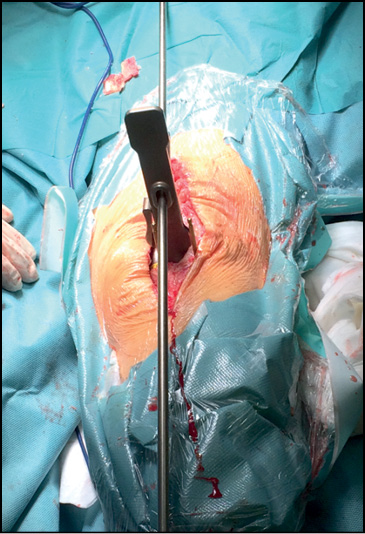

Затем первый индивидуальный резекционный блок с фиксирующими пинами удаляется, и на мыщелки большеберцовой кости устанавливается второй индивидуальный резекционный блок (рис. 3). В данном случае, чтобы сохранить минимальную конфигурацию индивидуального резекционного блока и исключить расширение границ оперативного доступа, предусмотрены только отверстия для четырёх ориентирующих пинов. Однако при более благоприятных условиях в конфигурацию второго индивидуального резекционного блока возможно добавление прорези для выполнения опила мыщелков большеберцовой кости.

Рис. 3. Установка второго индивидуального резекционного блока на мыщелки большеберцовой кости.

Fig. 3. Fixing the second individual resection block on the tibial condyles.